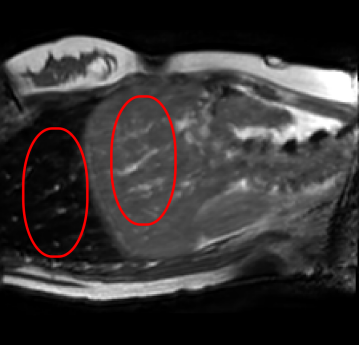

Figure 1: (a) Ground truth and (b,c) interpolated images from (b) baseline (SCIN) and (c) proposed method (MFIN). The image interpolated via SCIN is heavily blurred and misses several lung and liver structures, while the proposed method is able to preserve the details in the ground truth image.

Qualitative results are shown in Fig. 4. We observe no large qualitative differences in the performances of MFIN and MFINc for either loss function. Since, MFINc-SSIM provides the best quantitative results, we show interpolated images from this method and compare them against SCIN-SSIM. Both methods perform well when the motion between the neighbouring images is low. This is reflected in the absence of any structures in the error images in Fig. 4.1. However, RMSE is lower for SCIN because it produces a denoised interpolated image, while MFIN carries over the noise pattern from the neighbouring known image. Whenever there exists high motion between the images being interpolated, SCIN produces blurry images and often misses image structures. This can be observed in cases 2-4 in Fig. 4. For all these cases, MFINc (and also MFIN) produces sharp images and largely preserves structures in the images. Fig. 4.2 shows a case where MFINc additionally has a much better performance with respect to image alignment. Fig. 4.3 shows a representative case, with small improvement in image alignment, yet worse RMSE and SSIM values for MFINc. Finally, Fig. 4.4 shows a case, where MFINc produces worse alignment of structures than SCIN.